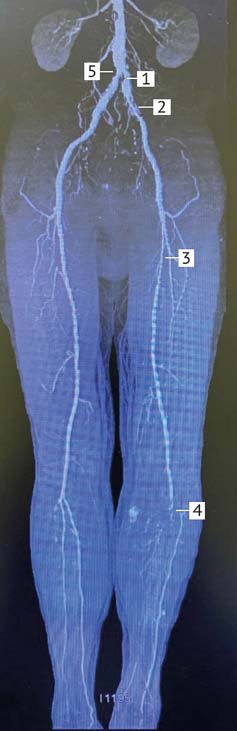

Figure 3 shows a computer angiogram of the lower extremities arteries from patients with chronic critical ischemia of the left lower extremities, caused by atherosclerotic stenosis of the left common iliac artery 80% (1), left external iliac artery 95% (2), left superficial femoral artery 95% (3) and proximal occlusion of the tibial and fibular arteries (4). The patient also revealed a narrowing of the proximal right common iliac artery 70% (5).

Fig. 3. Computer angiogram of the arteries of the lower extremities of a patient with chronic critical ischemia of the left lower limb. Stenosis of the left common iliac artery 80% (1), left external iliac artery 95% (2), left superficial femoral artery 95% (3) and proximal occlusion of the tibial and fibular arteries(4), stenosis of the proximal right common iliac artery 70% (5)